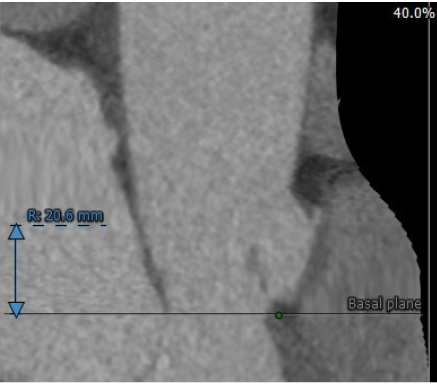

冠脉高度尚可。左冠高度:13.4,右冠高度:20.6。心脏角度52